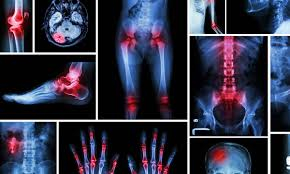

FINAL ST3 Orthopaedic Interview 2025 Mock Interview Dates Added!

Due to demand we are adding extra dates for our extremely popular ST3 Trauma and Orthopaedic Mock Interviews for 2025.